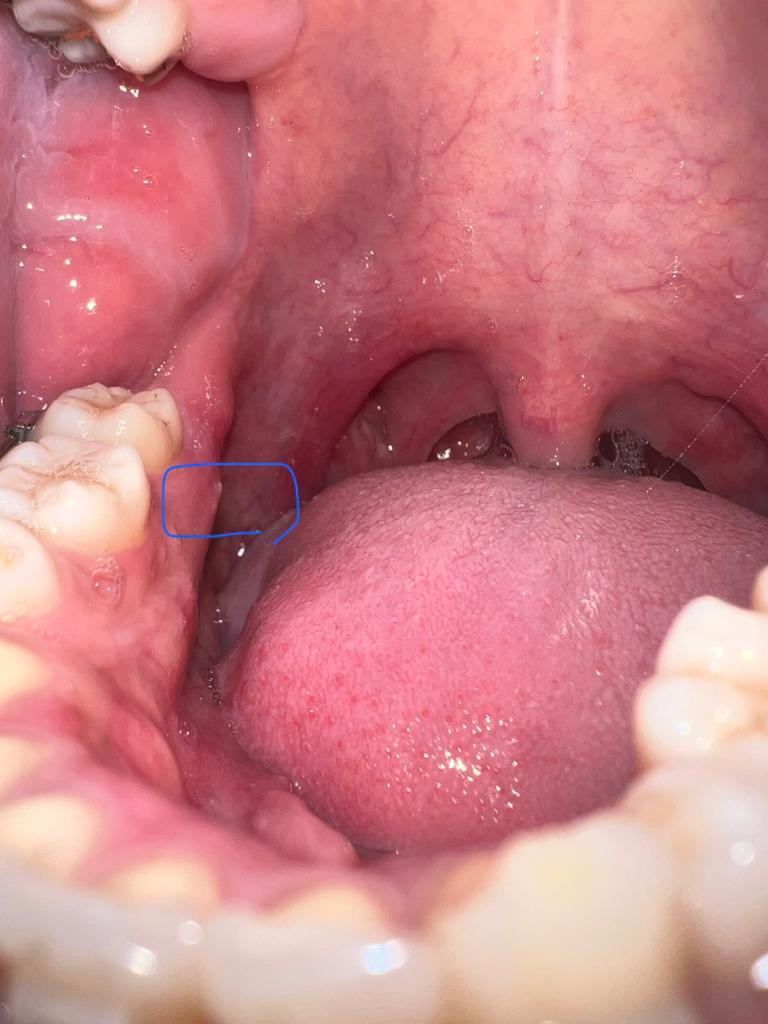

잇몸 골융기가 났는데 통증이 있을 수 있나요??

한달전에 잇몸에 뼈가 자라더니 뭐랄까 좀 욱신욱신거리는 통증이있네요 ㅠ 그리고 저쪽 하얀색 튀어나온곳에서 고름이 나와 4일전 치과로 방문해서 보고 만지시더니 뼈라고 하시더라구요 그러고 치근단 엑스레이 촬영 후 치근단 염증은 아니라고 단순 궤양이라고하시고 항생제랑 소염진통제만 주시고 5일뒤에 다시오라고하시더라구요 ㅠ 고름은 이제 잘 안나는거같은데 통증은 변함없네요 ㅠㅠ 나이는 24살입니다 큰 병일까봐 걱정되서 작성해봅니다

• 1번 째 사진

뼈가 튀어 나와서 자극을 받아서 그러는거 같습니다. 계속해서 불편하시면 마취하고 튀어나온 부분을 다듬으시면될것같습니다.

뼈가 튀어나와서 입안으로 돌출되다보니 구내염처럼 큰 불편감을 주는 경우인것 같습니다.

만약 계속 상처가 아물지 않는다면, 치과에서 뼈가 튀어나온부위만 살짝 다듬으면 한결 빠르게 치유될 수 있는데, 해당부(혀쪽)으로는 중요한 해부학적 구조물(설신경,혈관 등)이 지나가기 때문에 치과에서 치과의사의 정확한 진단후 치료가 가능합니다.

일단 우툴두툴한 표면은 뼈의 형태로 인한 것이 맞는 것 같습니다

일반적인 골융기는 특별히 자극이 가해지지 않는이상 통증이 있을 일이 없고 잇몸 염증에 의해서는 통증이 있을 수 있습니다